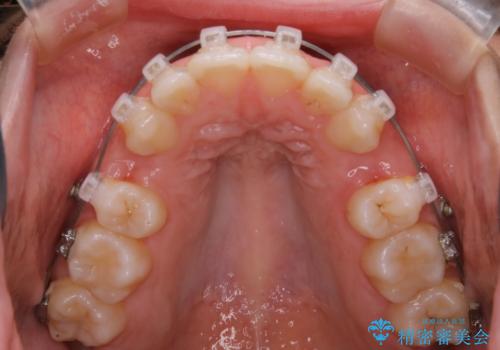

- ワイヤー(クリア装置)

しっかりと口元・顔貌まで変化を起こせるように上下左右の第一小臼歯を抜歯し、ワイヤー装置にて矯正を開始することとなりました。